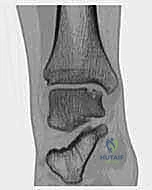

- التصوير بالرنين المغناطيسي (MRI): هو المعيار الذهبي (Gold Standard) لتشخيص OLTs. يُظهر الرنين المغناطيسي الغضروف بدقة عالية، ويحدد حجم الآفة، عمقها، وحالة العظم تحت الغضروفي (مثل وجود وذمة عظمية - Bone Marrow Edema).

- الأشعة المقطعية (CT Scan): يطلبها الدكتور هطيف أحياناً للحصول على خريطة ثلاثية الأبعاد دقيقة للعظم، مما يساعد في التخطيط الجراحي وتحديد حجم الرقعة العظمية المطلوبة للزرع.

جدول 1: تصنيف آفات القبة الكاحلية (تصنيف بيرندت وهارتي المُعدل)

لتبسيط فهم مدى خطورة الحالة، يستخدم الأطباء أنظمة تصنيف عالمية. إليك الجدول التوضيحي:

| المرحلة الأولى (I) | انضغاط بسيط في العظم تحت الغضروفي (كدمة عظمية) دون تمزق السطح الغضروفي. | ألم خفيف بعد المجهود، لا يوجد تورم ملحوظ. | علاج تحفظي (راحة، ثلج، علاج طبيعي). |

| المرحلة الثانية (II) | انفصال جزئي لقطعة من الغضروف والعظم، لكنها لا تزال متصلة جزئياً في مكانها. | ألم متوسط، تورم متقطع، ألم عند الضغط المباشر. | علاج تحفظي مكثف، أو تدخل جراحي طفيف. |

| المرحلة الثالثة (III) | انفصال كامل للقطعة الغضروفية العظمية، لكنها باقية في مكانها (لم تتحرك داخل المفصل). | ألم شديد، تصلب، شعور بعدم الاستقرار. | تدخل جراحي (تثقيب دقيق أو زرع). |

| المرحلة الرابعة (IV) | انفصال كامل للقطعة، وخروجها من مكانها لتسبح كـ "جسم حر" (Loose Body) داخل المفصل. | ألم حاد، قفل المفصل (Locking)، عدم القدرة على المشي. | تدخل جراحي فوري (إزالة الجسم الحر + زرع غضروفي). |